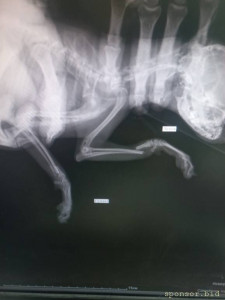

🆘🆘🆘 ПОМОГИТЕ ОПЛАТИТЬ ОПЕРАЦИЮ! Маленький той , сломала две передних лапки. Лапки просто отломленный, болтаются. Срочно нужно прооперировать🤧Стоимость такой операции 28 тыс. рублей, одна лапка 12-14 тыс ((((( Друзья, помогите поставить девочку на лапки 🙏🏻🙏🏻🙏🏻

Помогите сохранить лапки тойчику 128591; - 1682859004353.jpg

Помогите сохранить лапки тойчику 128591; - 20230419_204628.jpg

Помогите сохранить лапки тойчику 128591; - 20230419_204647.jpg

Помогите сохранить лапки тойчику 128591; - Screenshot_20230430-163919.jpg

Помогите сохранить лапки тойчику 128591; - Screenshot_20230430-163547.jpg